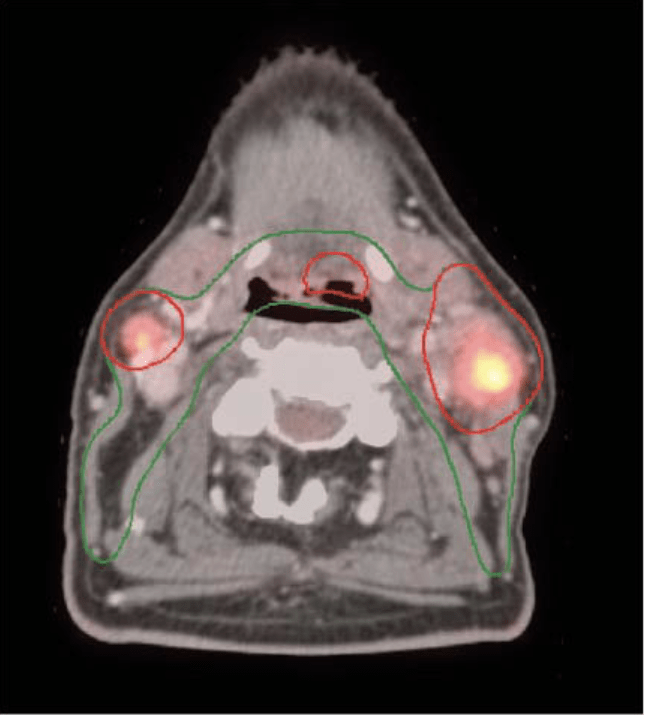

Radiation Planning: MSKCC Contouring & Dose Specifications

Target Volume Definitions

- Post-op cavity + 5-10 mm margin

- Include pre-op GTV extent

- Tonsil:Â Include ipsilateral pterygoid plates

- BOT:Â Include pre-epiglottic space

- Unknown primary:Â Entire oropharyngeal axis

CTV Nodal:

- Gross nodes + 5 mm (no additional margin if >3cm)

- Entire involved nodal level

- No intentional ECE coverage required

CTV Elective:

- Bilateral levels II-IV (standard)

- Level IB if oral cavity involvement

- Retropharyngeal if posterior pharyngeal wall

- Well-lateralized T1-2 tonsil + single node → ipsilateral only

Dose Prescription

ALL PATIENTS - First 30 Gy:

- PTV_3000: All volumes (primary, nodes, elective)

- 2 Gy Ă— 15 fractions = 30 Gy

- Delivered regardless of hypoxia status

HYPOXIA NEGATIVE/RESOLVED (84%):

- Stop at 30 Gy total dose

- 3 weeks total treatment time

PERSISTENT HYPOXIA (16%):

- PTV_7000: Hypoxic gross nodes only

- Additional 2 Gy Ă— 20 fractions = 40 Gy boost

- Total 70 Gy to hypoxic nodes

- 7 weeks total treatment time

Planning Specifications

- Technique:Â IMRT (VMAT acceptable)

- PTV margins:Â 3-5 mm from CTV

- Coverage:Â 95% of PTV receives 95% of Rx dose

- Hot spots:Â <107% within PTV, <110% point max

- Plan review:Â 2 radiation oncologists (N.Y.L. and N.R.)

Critical Innovation:Â Universal elective dose of 30 Gy (vs historical 50-63 Gy) dramatically reduces toxicity while maintaining excellent regional control. This represents a paradigm shift in elective nodal treatment.